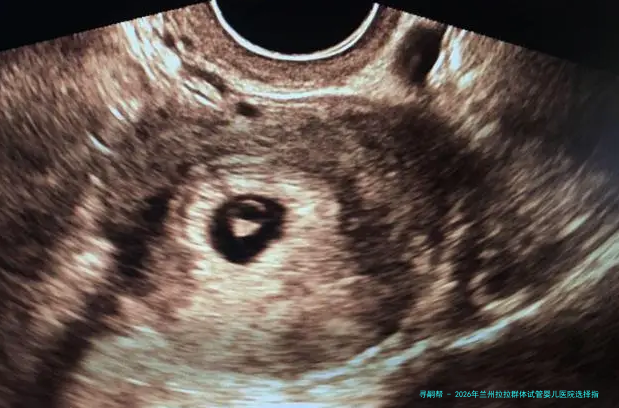

2026年兰州拉拉群体试管婴儿医院选择指南:附本地生殖中心服务特色与医生专长解析